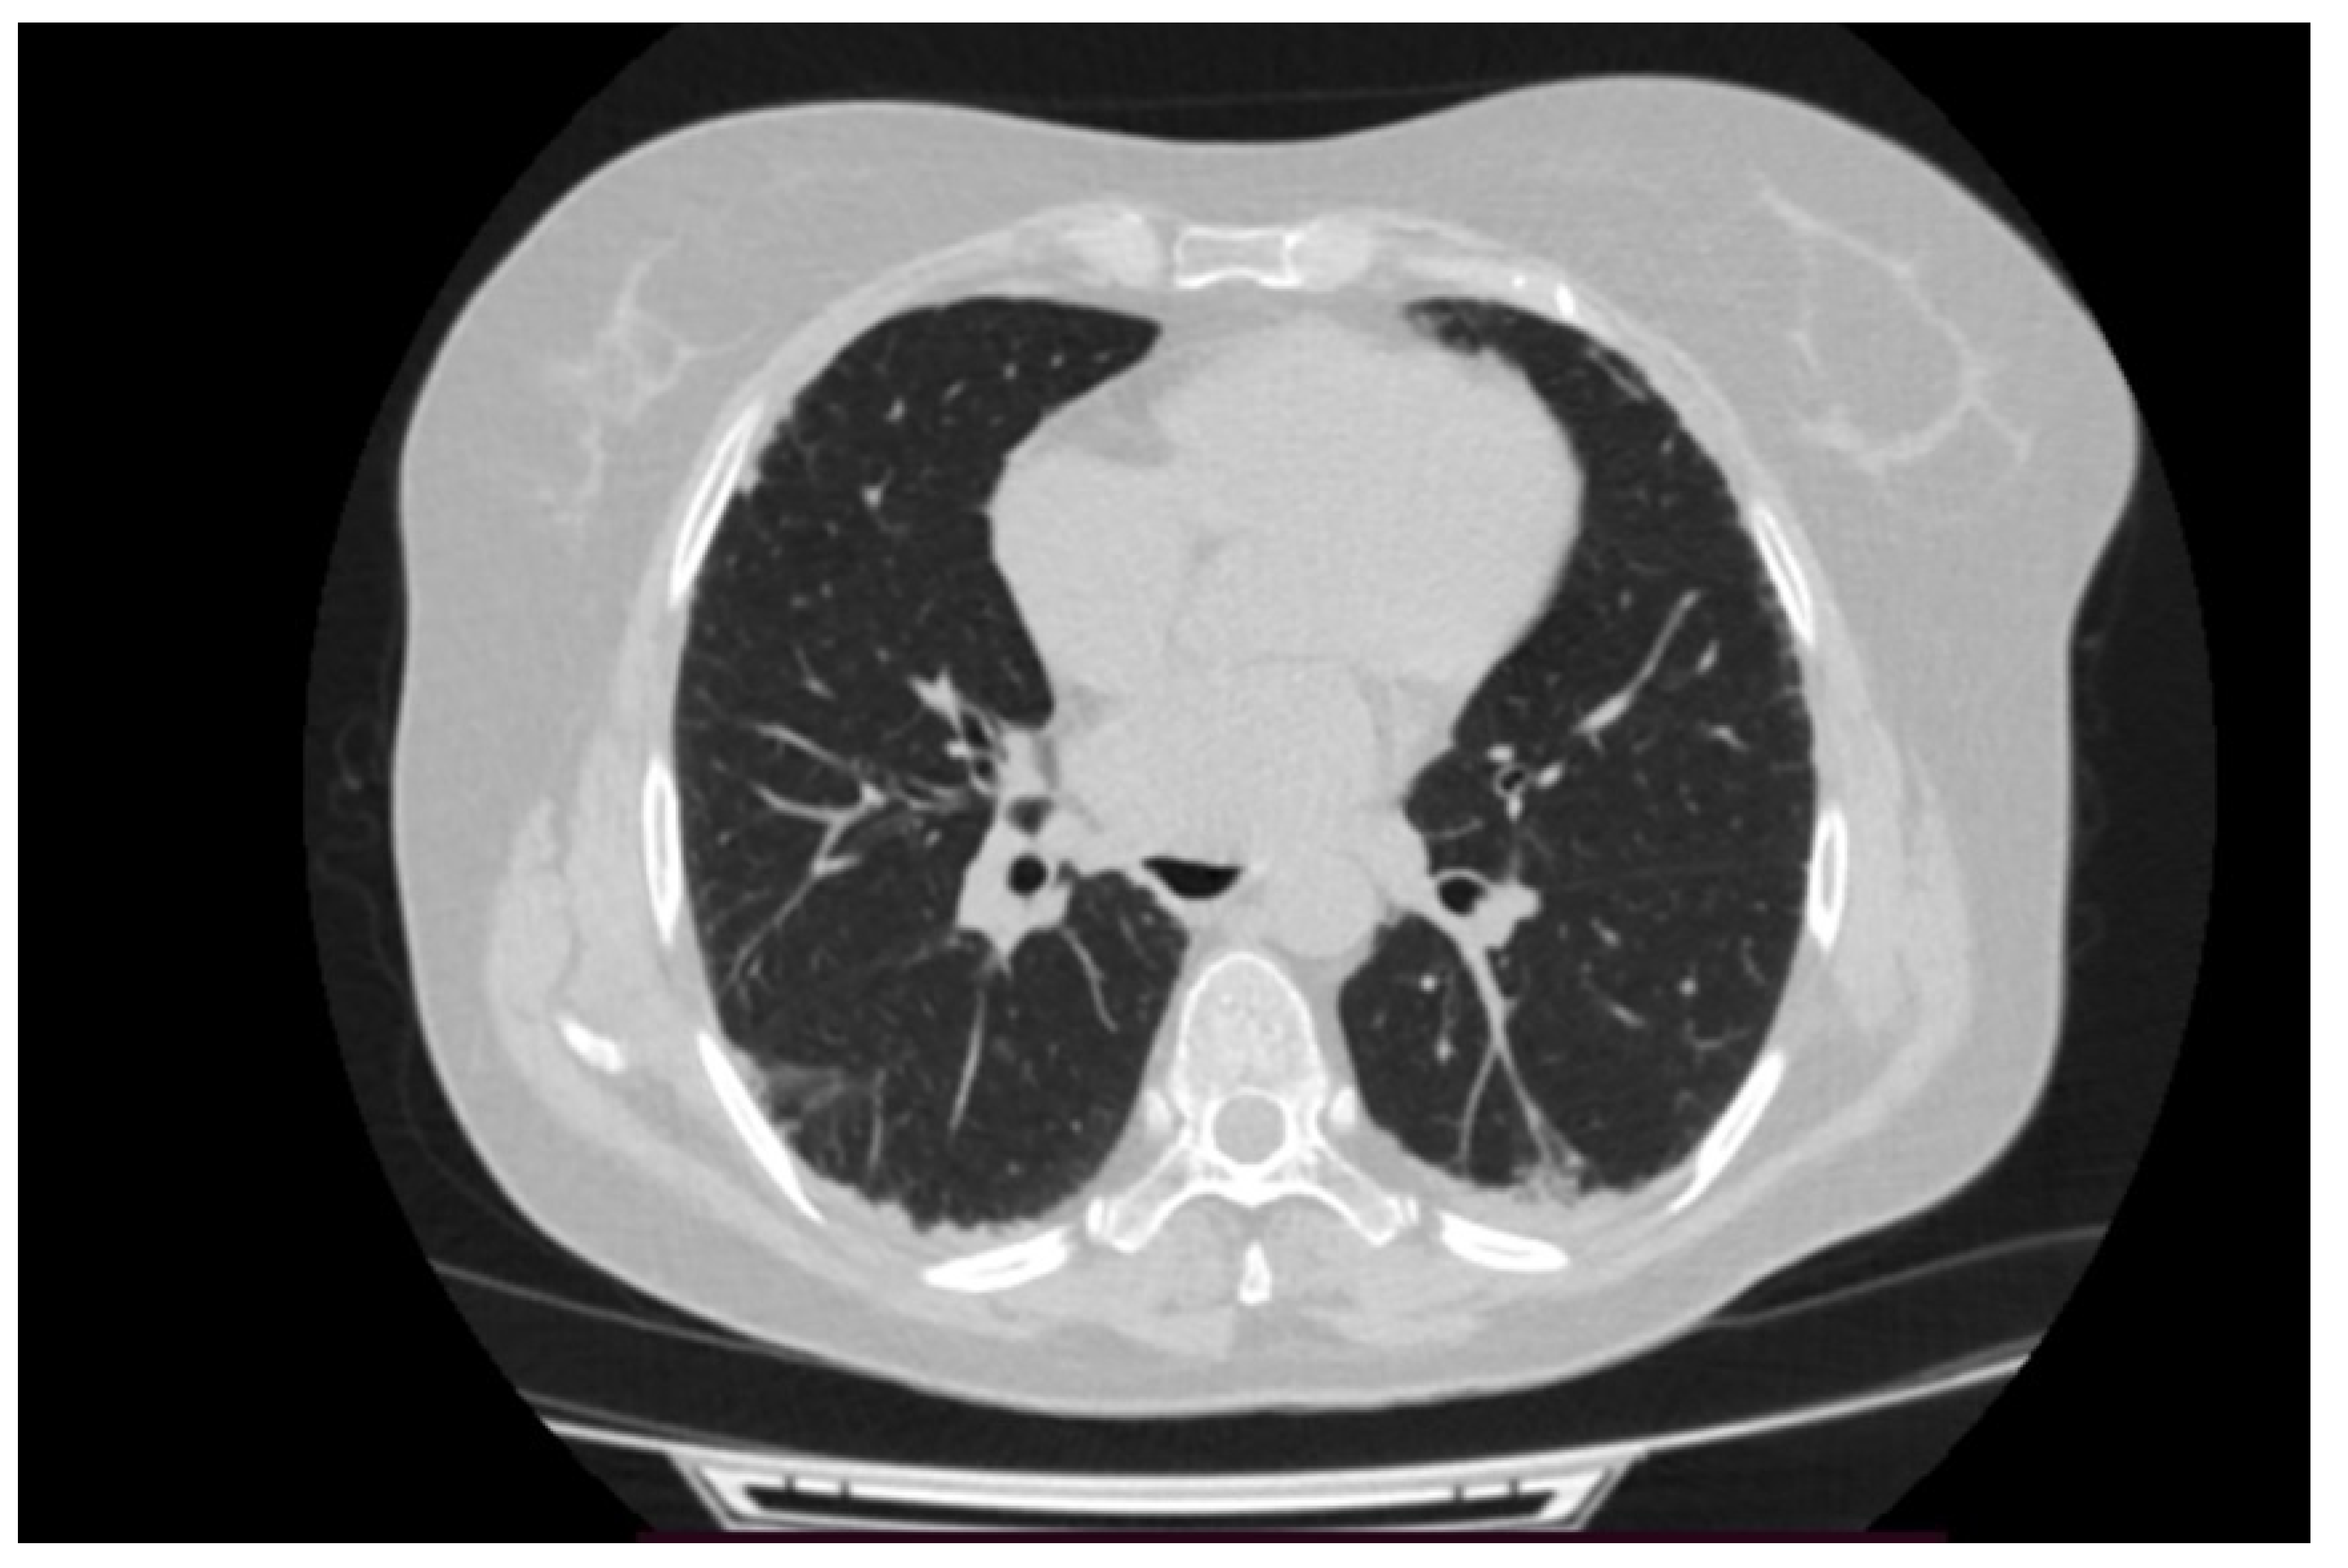

2. Case Presentation

4.2. Early Pulmonary Involvement in Antisynthetase Syndrome—Diagnostic and Prognostic Value